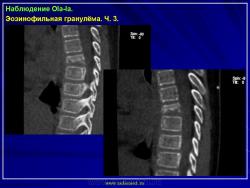

Из опубликованных наблюдений н сайте.